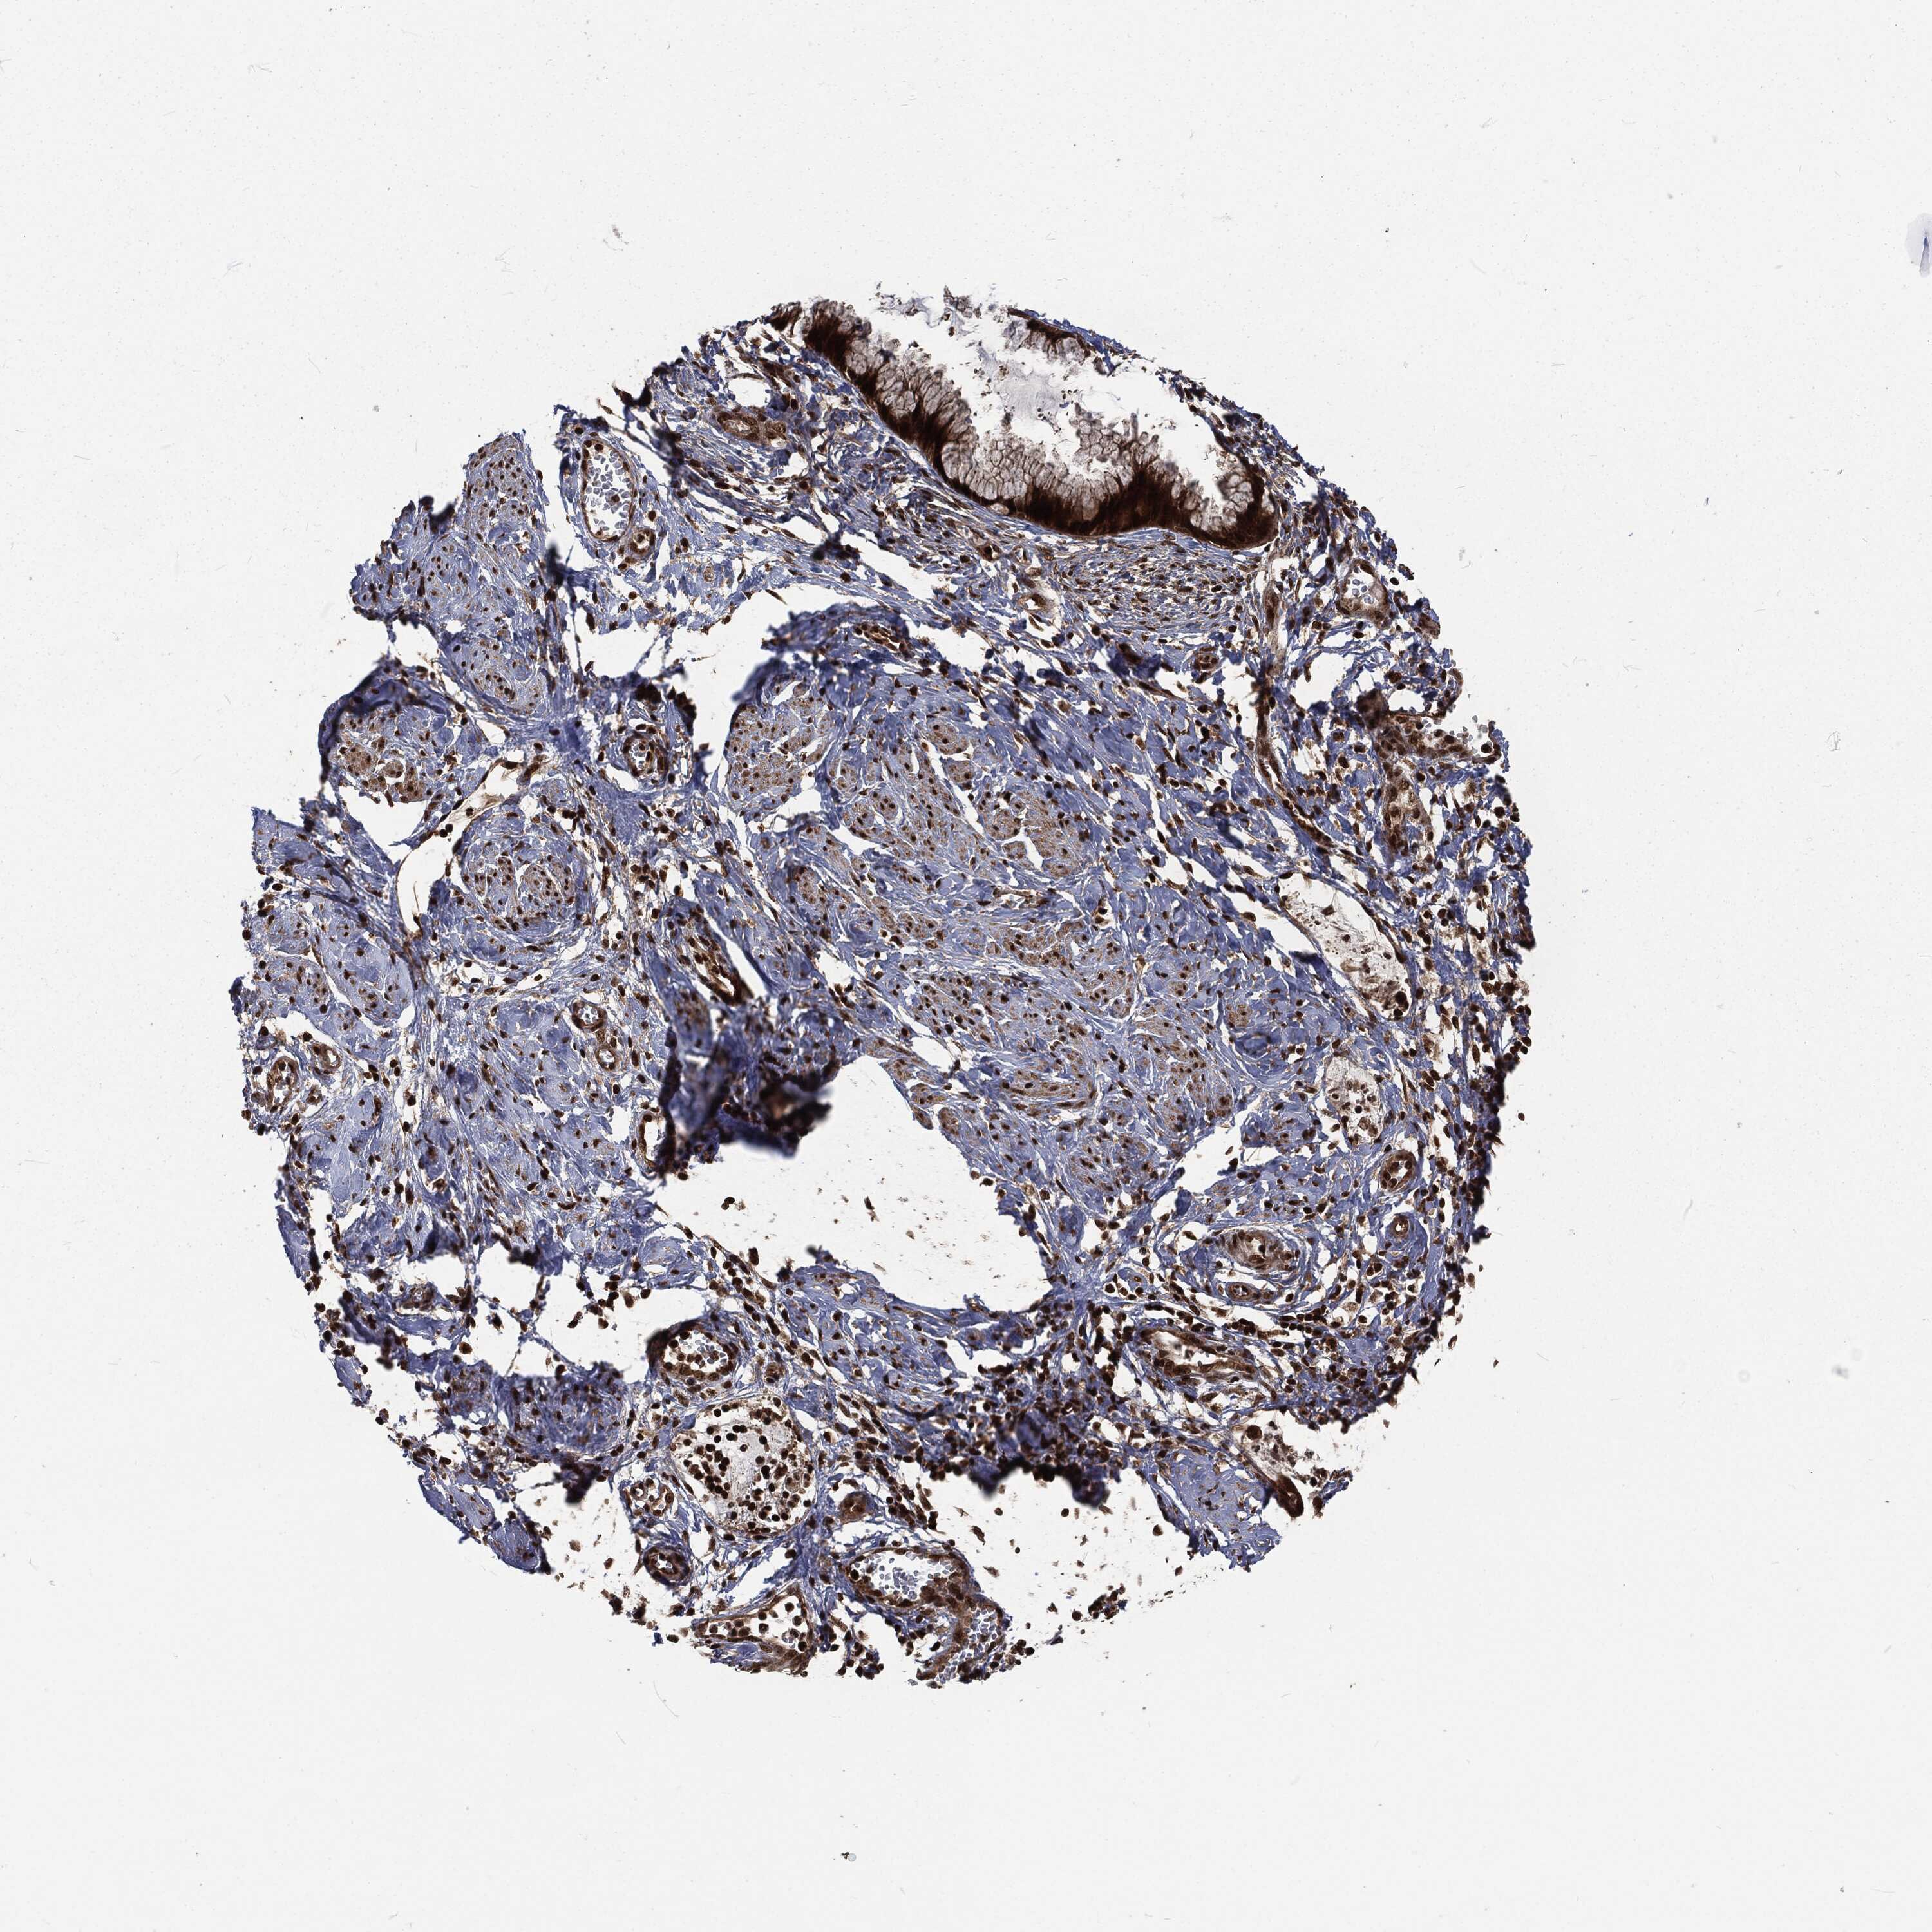

CERVICAL CANCER - Protein expressioni

A mouse-over function shows sample information and annotation data. Click on an image to view it in a full screen mode. Samples can be filtered based on level of antibody staining by selecting one or several of the following categories: high, medium, low and not detected. The assay and annotation is described here.

Note that samples used for immunohistochemistry by the Human Protein Atlas do not correspond to samples in the TCGA dataset.

Antibody stainingi

Antibody staining in the annotated cell types in the current human tissue is reported as not detected, low, medium, or high, based on conventional immunohistochemistry profiling in selected tissues. This score is based on the combination of the staining intensity and fraction of stained cells.

Each image is clickable and will lead to virtual microscopy that enables deeper exploration of all samples and also displays staining intensity scores, fraction scores and subcellular localization as well as patient and tissue information for each sample.

Antibody HPA041367

Antibody HPA076267

Staining

High

Medium

Low

Not detected

Intensity

Strong

Moderate

Weak

Negative

Quantity

>75%

75%-25%

<25%

None

Location

Nuclear

Cytoplasmic/membranous

Cytoplasmic/membranous,nuclear

Squamous cell carcinoma, NOS

Adenocarcinoma, NOS